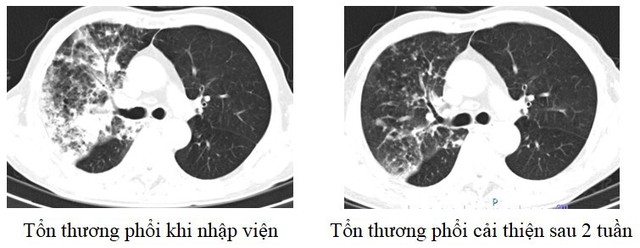

Hình ảnh phổi của người bệnh trước và sau khi điều trị. Ảnh: BVĐK Phú Thọ.

Mới đây nhất là trường hợp người bệnh nữ 48 tuổi, địa chỉ ở Lập Thạch, Vĩnh Phúc vào viện vì ho khạc đờm, sốt cao. Xét nghiệm máu cho thấy chỉ số viêm tăng cao, chụp phổi ghi nhận đông đặc diện rộng phổi trái.

Hay trường hợp người bệnh nam 75 tuổi ở Hạ Hòa, Phú Thọ có tiền sử tăng huyết áp vào viện vì ho khạc đờm, khó thở. Chụp phim cho thấy tổn thương viêm diện rộng phổi trái. Do người bệnh cao tuổi, lại có nhiều bệnh nền nên thời gian điều trị kéo dài. Sau 2 tuần, sức khỏe người bệnh mới ổn định và được ra viện.